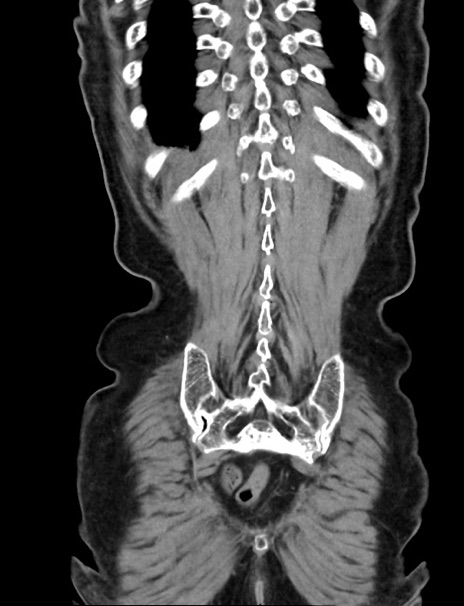

症例33(冠状断像)

【症例】70歳代 女性

【主訴】心窩部痛

【現病歴】延髄病変の精査・加療にて神経内科入院中。本日より心窩部痛あり。

【身体所見】右下腹部を中心に圧痛と反跳痛あり。

【データ】WBC 10900、CRP 0.02